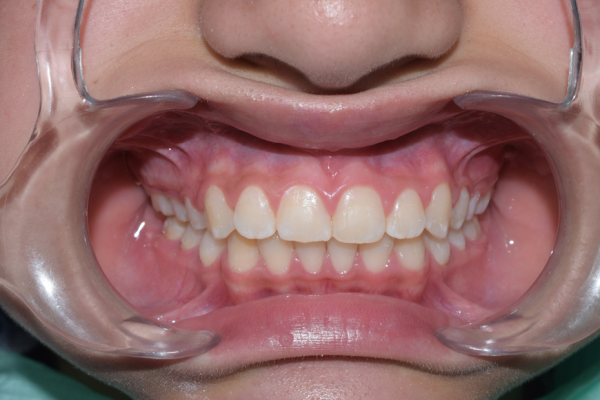

El paciente feliz, al finalizar su tratamiento

Cuando no se corrige a tiempo, este tipo de problema puede provocar:

- Mayor grado de apiñamiento en la adolescencia

- Tratamientos más largos y complejos

- Problemas en la mordida y función

- Riesgo aumentado de caries y enfermedad periodontal